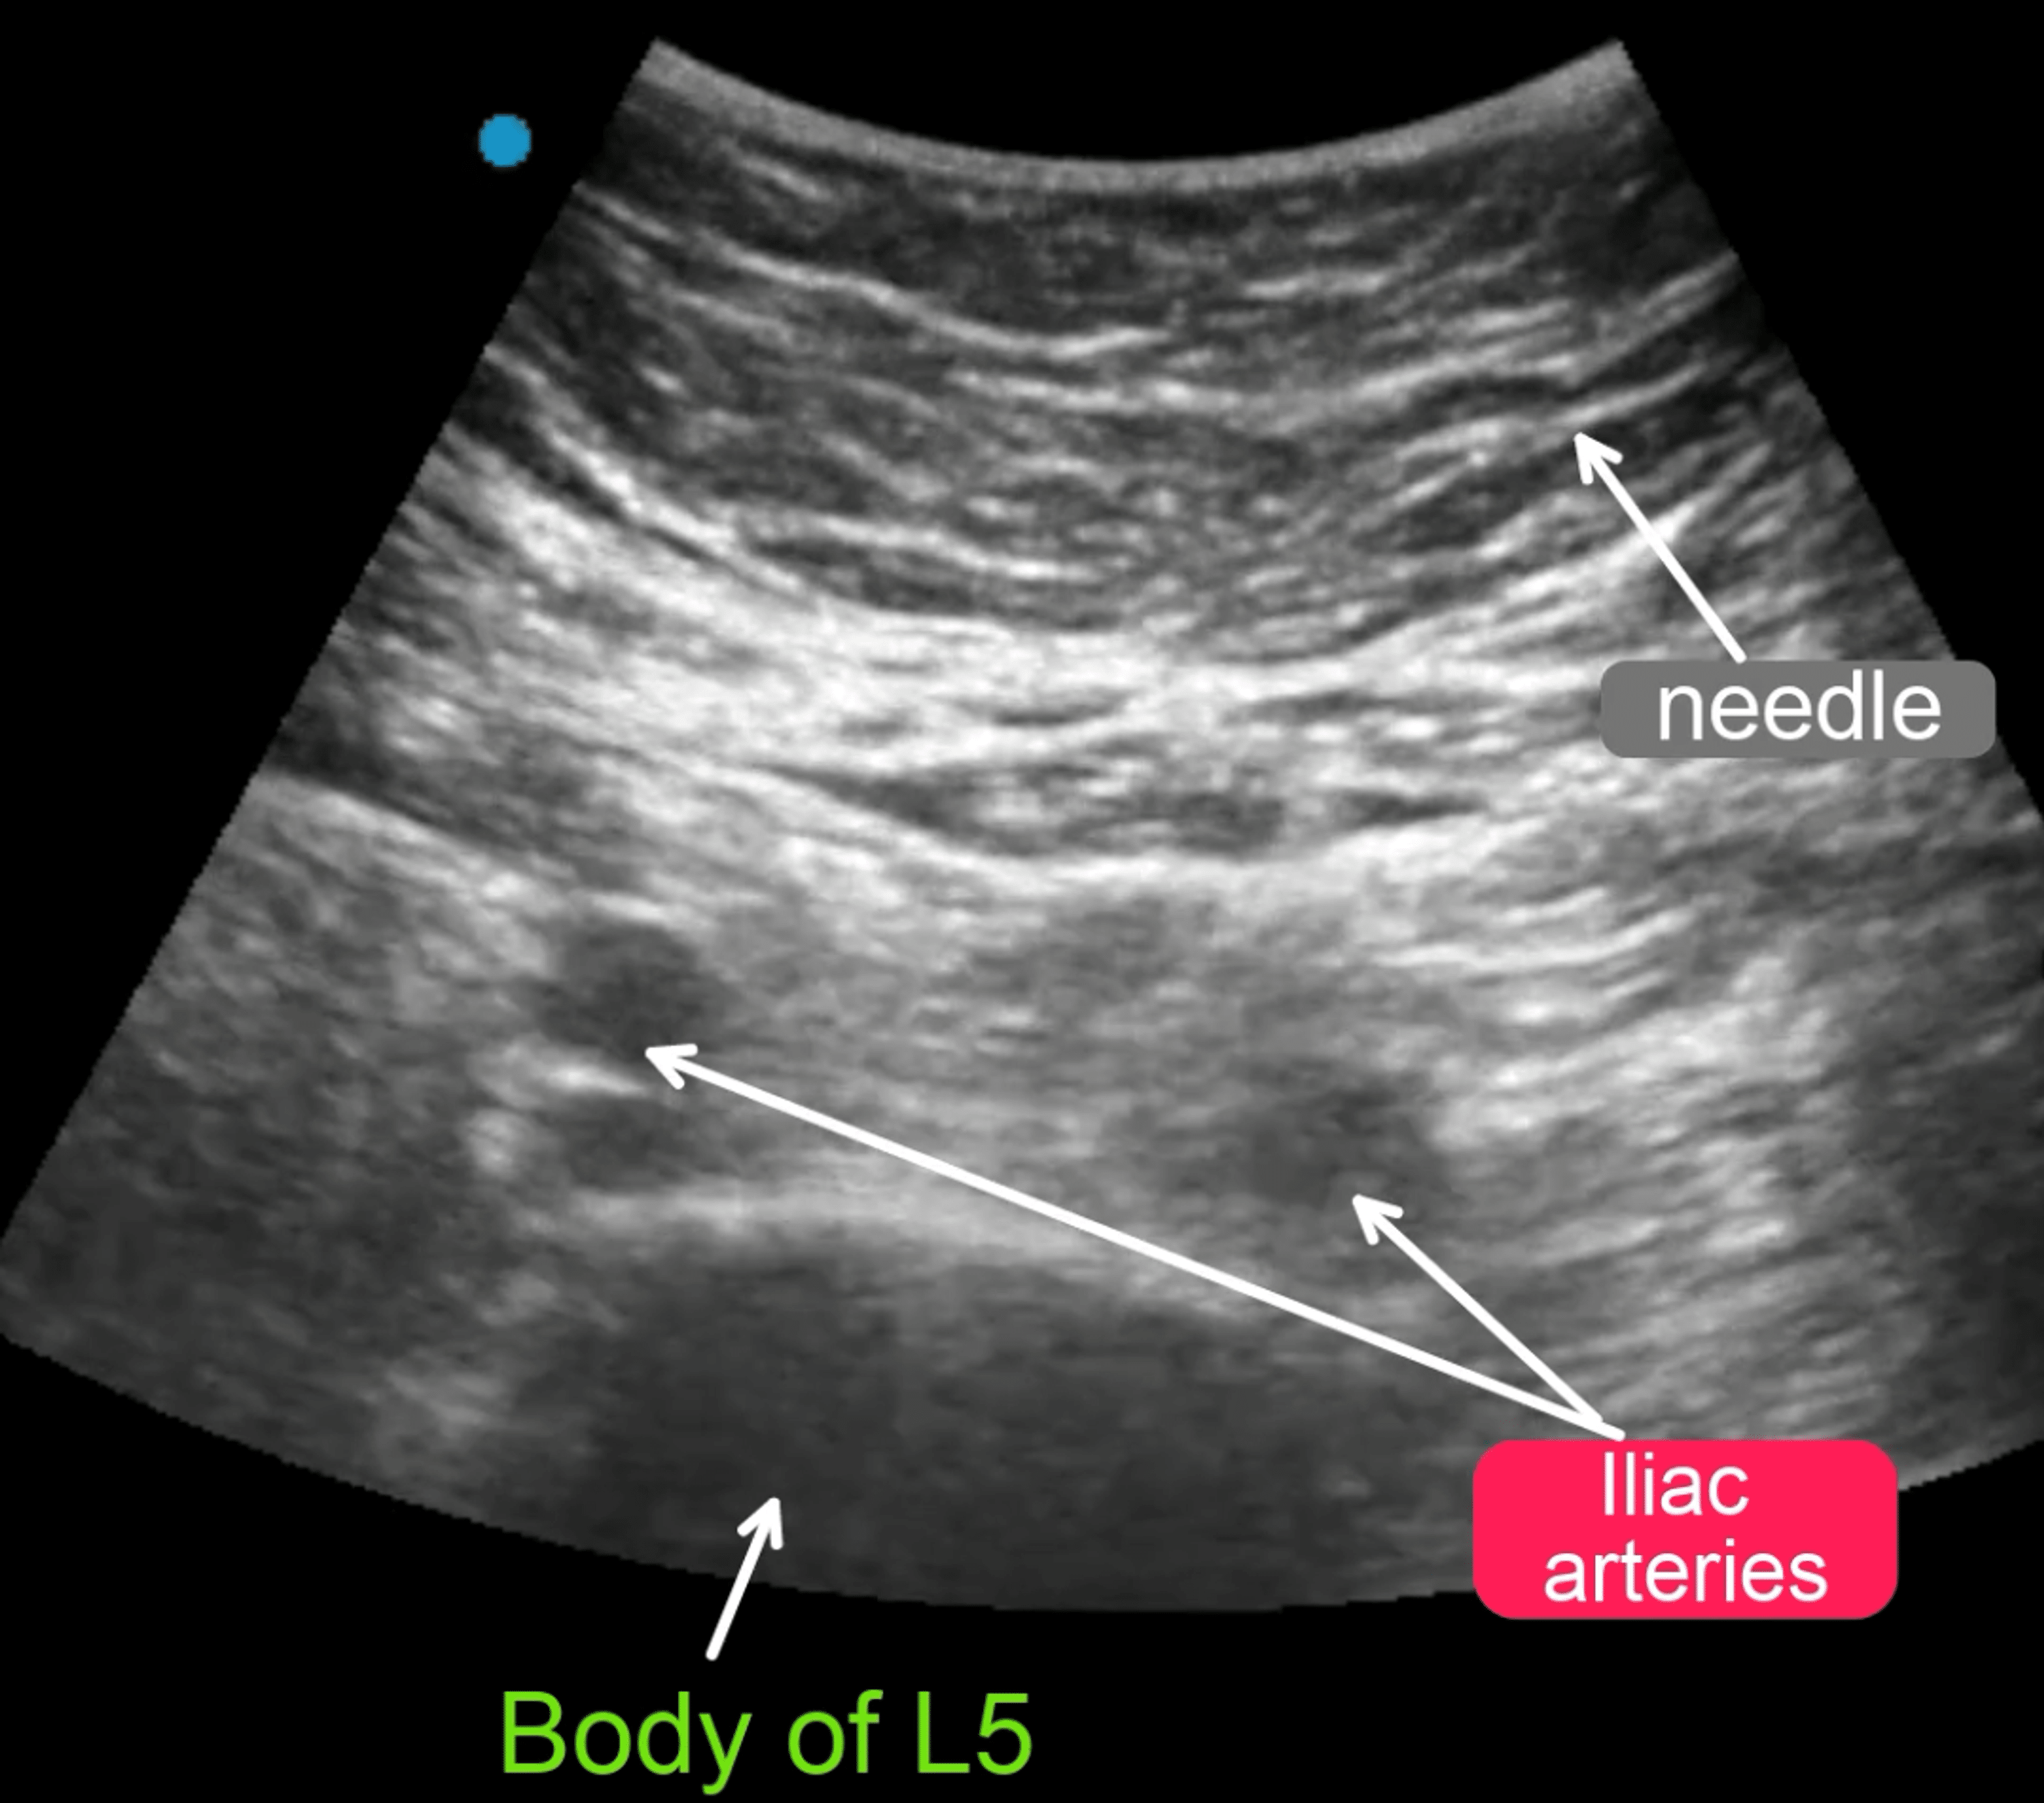

Cureus | Efficacy of Pudendal Nerve Blocks and Ultrasound ...